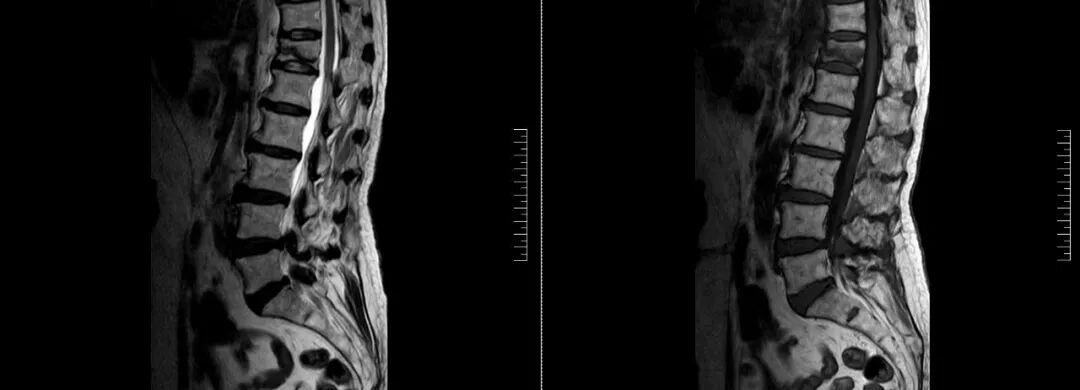

术前磁共振检查提示腰1椎体新鲜压缩性骨折

经术前分析详细评估,由骨科副主任张宏宇及科室团队顺利为患者进行了经皮穿刺椎体成形术,术后患者疼痛明显减轻。同时,科室团队还为她制定了科学的抗骨质疏松治疗,目前患者已康复出院。